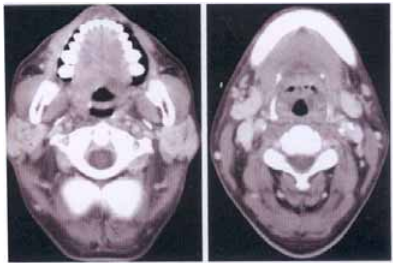

71 NPC 患者經過放射線治療六個月後,追蹤的 CT 如圖顯示 NPC 已消失,但意外發現雙側 parotid glands 及 submandibular glands 有不正 常超強的顯影劑 enhancement,這是:

(A)可能因 NPC invasion (B)可能是 metastatic lymphadenopathies (C) Infectious sialadenitis (D) Radiation sialadenitis

72 17 歲陳小姐,因罹患惡性淋巴瘤病(malignant lymphoma) 到醫院治療。醫師為她做腹部電腦斷層攝影檢查,發現卵 巢病灶如圖示。圖為注射對比劑後 CT,病灶 CT 值不變。 她的卵巢最可能罹患:

(A)子宮外孕(ectopic pregnancy) (B)卵巢囊腫(ovarian cyst) (C)卵巢癌(ovarian cancer) (D)惡性淋巴瘤病(malignant lymphoma)